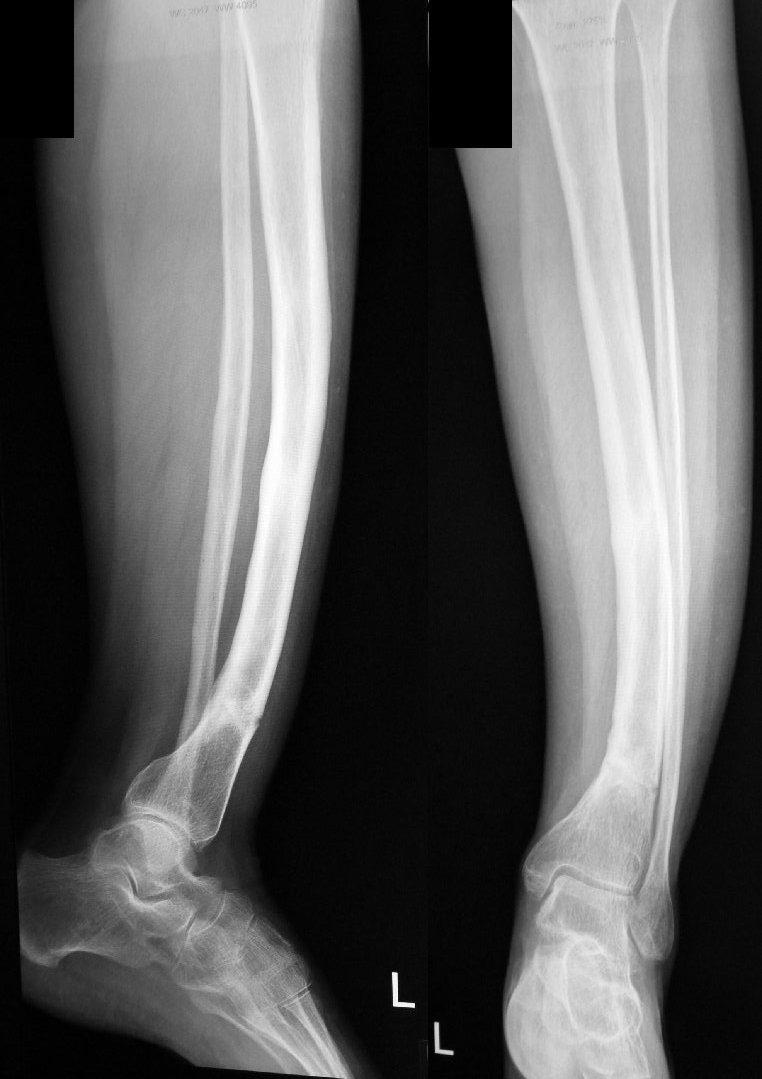

Врожденная патология голени - помощь в тактике лечения

Пациентка 1962 г.р. данная патология костей голени с детства, планировалось оперативное лечение в 18 лет (Вредена),

операцию отменили, рекомендовали консервативное лечение. рентгенограммы 2018-2019гг.

Врожденная патология голени

ещё рентгенограммы